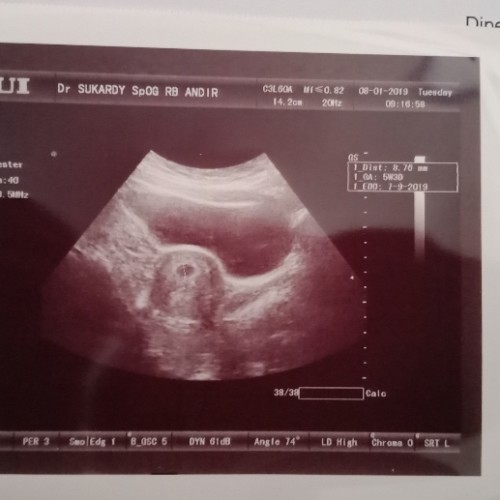

itu foto usg waktu usia kandungan saya 5 weeks bun,jadi kalo 5 weeks baru berbentuk titik kecil aja bun,masih embrio namanya belum jadi janin,masih darah yg menggumpal

kalo kantong janinnya sudah kelihatan bund mulai UK 4minggu udah ada penebalan dinding rahim. kalo debaynya mulai kelihatan UK 8minggu bund.

Saya Usia 5 Minggu 2 hari kantung kelihatan.. usia 6 Minggu 2 hari detak jantung sdah terdengar

6w cma kelihatan kamtong ajj.. lw mau kelihatan janinny 8W bun udh kelihatan plus bedeyut jantungnya

Saat saya si 7w.3d sudah keliatan kantung, janin dan djj nya bun.. semoga kabar baik ya bundaa..

sudah bun, dulu saya pertama kali usg uk 4w udh keluatan kantung nya

Kalau kantongnya udah bun tp kalau janinnya kemungkinan belum